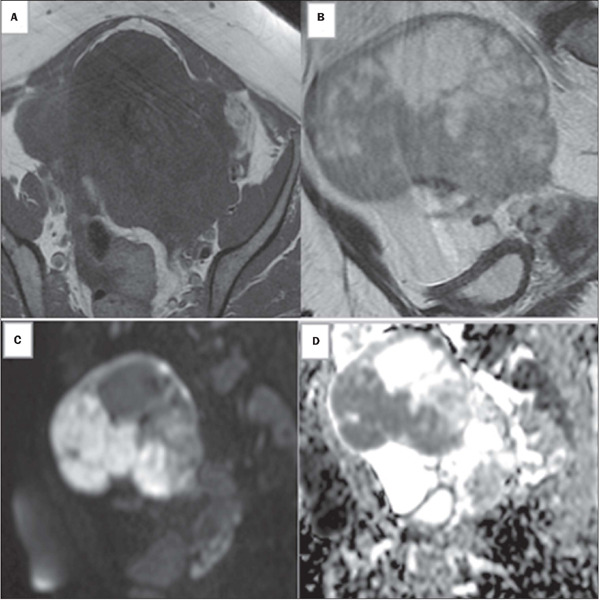

目的:探讨磁共振成像(MRI)对超声不确定卵巢及附件肿块分类的准确性。材料和方法:这是一项回顾性横断面研究,对243例共336例附件和卵巢肿块的未增强骨盆MRI扫描进行了回顾性研究。结果:未增强MRI的敏感性为97.7%,特异性为86.4%,准确率为93.8%。ROC曲线下面积为0.944 (95% CI: 0.913 ~ 0.974)。结论:我们的研究结果表明,非增强MRI方案可以用于对附件肿块进行分类,特别是在静脉注射钆造影剂不安全的临床环境中,应避免使用。

Objective: To investigate the accuracy of magnetic resonance imaging (MRI) in classifying sonographically indeterminate ovarian and adnexal masses.

Materials and methods: This was a retrospective cross-sectional study of the unenhanced pelvic MRI scans of 243 patients with a collective total of 336 adnexal and ovarian masses.

Results: Unenhanced MRI showed a sensitivity of 97.7%, a specificity of 86.4%, and an accuracy of 93.8%. The area under the ROC curve was 0.944 (95% CI: 0.913-0.974).

Conclusion: Our results show that an unenhanced MRI protocol can be used to classify adnexal masses, especially in clinical settings in which the intravenous administration of gadolinium-based contrast is not safe and should be avoided.